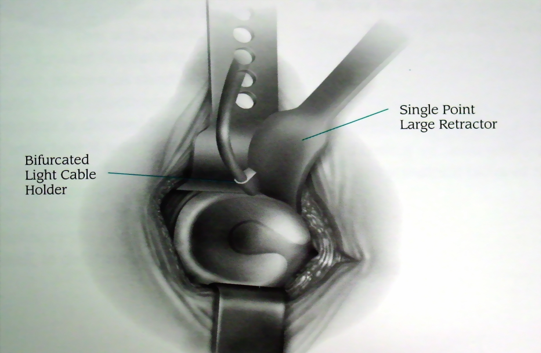

沿阔筋膜纤维方向切开扩筋膜大粗隆顶点臀中肌前1/3处沿纤维方向分离臀中肌

横形切开臀小肌2cm

沿大粗隆前缘切开臀中肌腱和臀小肌

切除关节囊髋关节内收、屈曲、外旋位脱位

准备髋臼

准备股骨髓腔

缝合切开之臀小肌和臀中肌